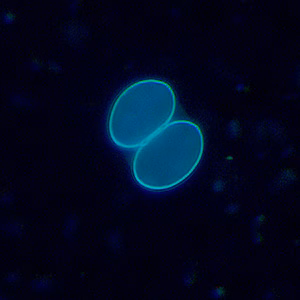

Both sporulated oocysts (containing two sporocysts) and individual sporocysts can be passed in stool

. Sporocysts contain four sporozoites and a refractile residual body. Sporocysts ingested by the intermediate host (cattle for S. hominis and pigs for S. suihominis) rupture, releasing sporozoites. Sporozoites enter endothelial cells of blood vessels and undergo schizogony, resulting in first-generation schizonts. Merozoites derived from the first-generation invade small capillaries and blood vessels, becoming second-generation schizonts. The second generation merozoites invade muscle cells and develop into sarcocysts containing bradyzoites, which are the infective stage for the definitive host

Sarcocystis oocysts in wet mounts viewed under ultraviolet (UV) microscopy.

For intestinal sarcocystosis caused by S. hominis and S. suihominis, diagnosis is made by the observation of oocysts or sporocysts in stool. They are easily overlooked as they are often shed in small numbers. Also, the two species cannot be separated by oocyst or sporocyst morphology. When humans serve as dead-end hosts for non-human Sarcocystis spp., diagnosis is made by the finding of sarcocysts in tissue specimens.